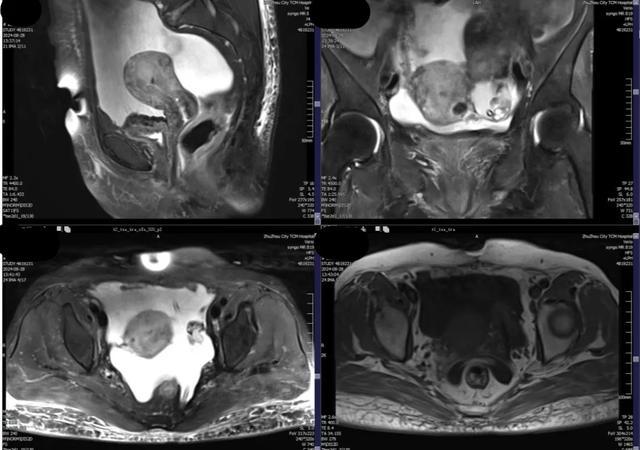

磁共振检查获取的是整个盆腔的数字信息,可以多方位、多参数的了解子宫及子宫肌瘤的情况,对于子宫肌瘤的生长发育情况以及是否影响后续生育更是有独到的见解,对于年轻的患者来说更是不可或缺的。

磁共振检查具有超高软组织分辨率,更是能够进行多方位、多参数的检查来评估病灶,给出更加精准的诊断意见,有利于盆腔肿块的发现、病变定性和肿瘤分期。

常规超声检查报告仅由检查描述、报告配图、结论构成,但是超声检查是一个动态获取过程,单靠文字以及配图无法完整复现检查中获取的信息量。与常规超声检查相比,磁共振检查一次检查能够获得整个盆腔的数字资料,更加客观准确的判断子宫肌瘤大小数目以及位置形态。

磁共振检查能够辅助判断一个病灶是良性还是恶性子宫肌瘤,通过磁共振增强检查可以使有血供的部位增强显影,一方面鉴别了肌瘤和肉瘤,一方面也能给临床医生更好的术前评估设计子宫切口,以合适的切口进行子宫肌瘤的剔除。